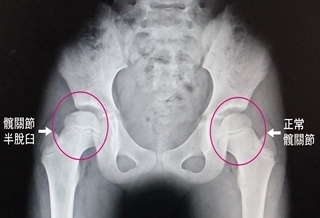

(優活健康網記者徐平/綜合報導)一名初學滑直排輪的8歲女童,屢屢摔倒,一直感覺右邊腹股溝疼痛,後來走路出現一跛一跛情況,就醫後經X光檢查發現,該女童的右側髖關節半脫臼,醫師提醒,髖關節半脫臼如未妥善治療,有可能會導致脊椎側彎或走路外八字的嚴重後果。假性長短腳 右腳有些微較短澄清醫院中港院區復健科主治醫師董莉貞表示,經髖關節外展理學檢查發現女學童的右側腹股溝部位有疼痛現象,而兩腳已出現假性長短腳,右腳有些微較短,強烈懷疑是髖關節的問題。做X光檢查,證實是右側髖關節半脫臼,從影像可以看出她的股骨頭有部分跑出髖臼之外,才造成腹股溝疼痛及假性長短腳現象,由於病情並不嚴重,建議立即進行復健治療。徒手進行髖關節展延並加強臀肌力量復健治療部主任蔡永裕指出,由於該女童的髖關節半脫臼導致關節活動角度受限,是一跛一跛走進復健治療部,經短波治療儀增加關節的延展性,再徒手進行髖關節展延運動並加強臀肌力量,讓半脫臼的髖關節即早恢復到原來的活動度,經持續2週復健治療,該女童已恢復正常走路姿態。臀部橫向皺痕不對稱 即早求醫孩童罹患髖關節半脫臼並不容易,除了先天性外,有可能因經常性的撞擊所造成,如果未接受妥善的復健治療,可能會導致脊椎側彎、跛行,董莉貞醫師強調,至於先天性的髖關節半脫臼,家長要細心觀察,如發現小孩兩側臀部橫向皺痕不對稱、長短腳、走起路來外八字像鴨子走路一樣,就要即早求醫,接受最適當的治療。